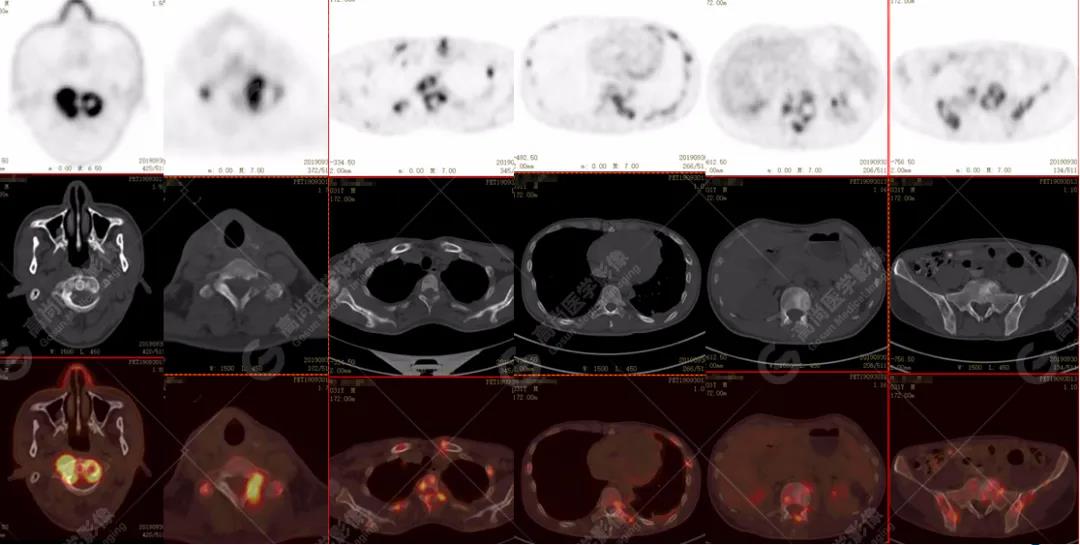

PET/CT全身圖

脊柱多發(fā)椎體及附件骨質(zhì)破壞,代謝不均性增高

全身多處骨質(zhì)破壞,代謝不均性增高

全身多發(fā)高代謝腫大淋巴結(jié),中央代謝缺損

左肺上葉尖后段及下葉背段多發(fā)簇狀斑點(diǎn)狀高代謝灶

左側(cè)胸膜結(jié)節(jié)樣增厚,代謝不同程度增高

雙肺、左側(cè)胸膜多發(fā)結(jié)節(jié)影,全身多處骨質(zhì)破壞,全身多發(fā)淋巴結(jié)腫大,代謝攝取不均勻性增高。